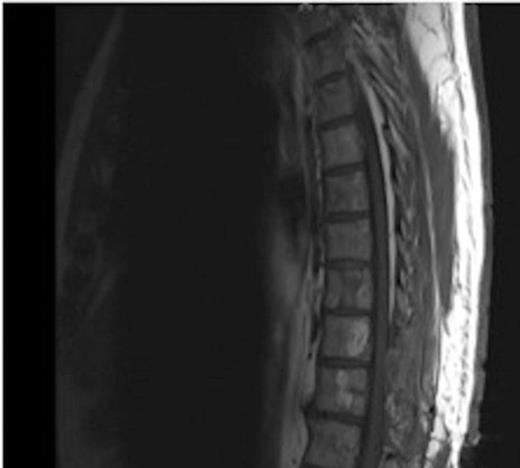

MRI showing the extra-dural tumour and extension into the soft tissue of the back

A one-year history of lower back pain, which was initially thought to be due to his liver metastasis, was investigated further with a full spine MRI scan. The scan revealed a large T10-11 extra-dural tumour with erosion of the T12 pedicle and extension into the soft tissue of the back. As a result of this discovery, the patient was referred for radiotherapy. Prior to commencement of this the oncologist requested a neurosurgical opinion from us.

MRI showing the T10-11 extra-dural tumour with erosion of the T12 pedicle